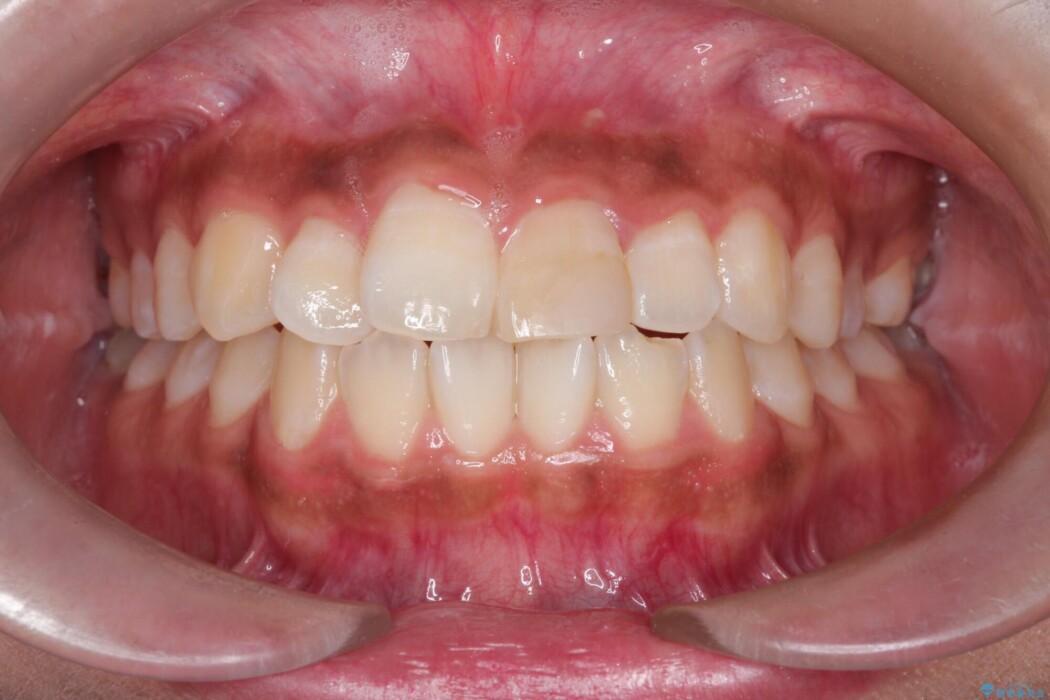

抜歯によって得たスペースを活用し、審美ワイヤーによる繊細な角度調整を行いながら前歯を後方へ移動。

突出していた口元のボリュームを段階的に抑制し、理想的なバランスへと導きました。

機能面では上下の緊密な咬合を確立し、審美面ではEラインの劇的な改善を実現しました。 形態と機能の両立により、患者様の満足度が非常に高い仕上がりとなりました。